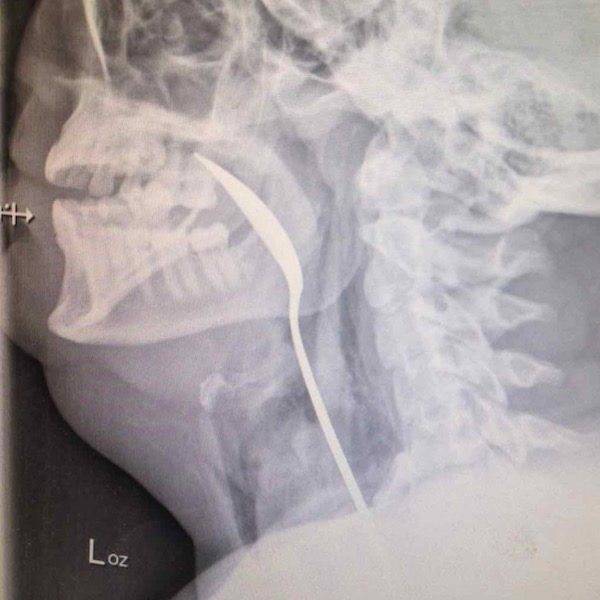

Man puts wire up his rectum to get stuck wine bottle.

Both get stuck. As ever.